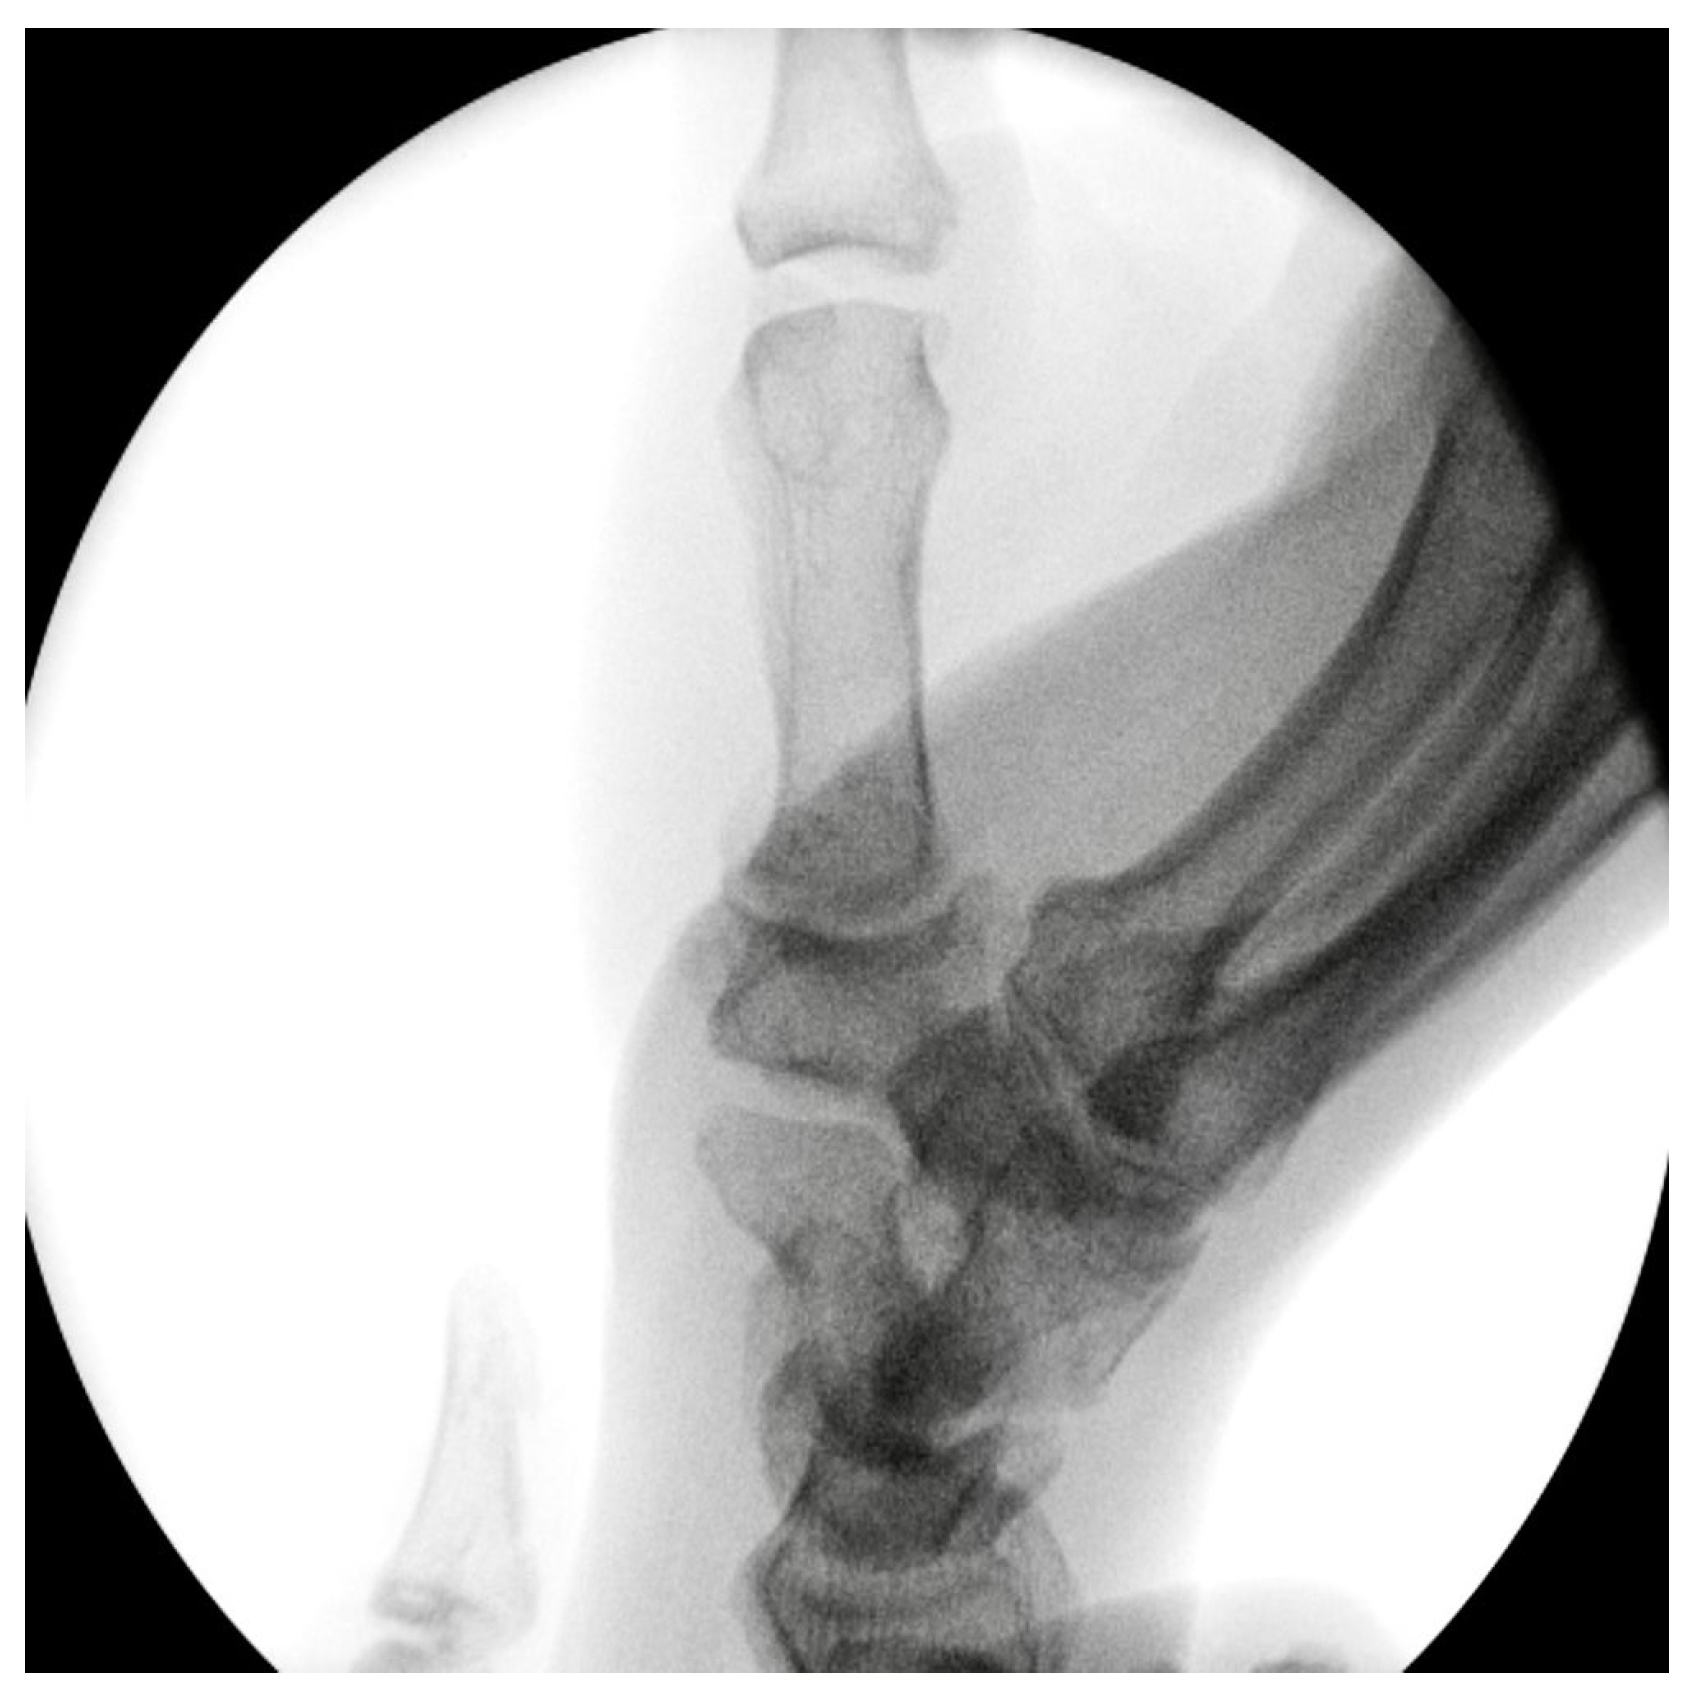

Primary Trapeziometacarpal (TMC) Arthroplasty for Bennett Fracture in Setting of Severe Thumb Osteoarthritis: A Case Report

2. Case Report